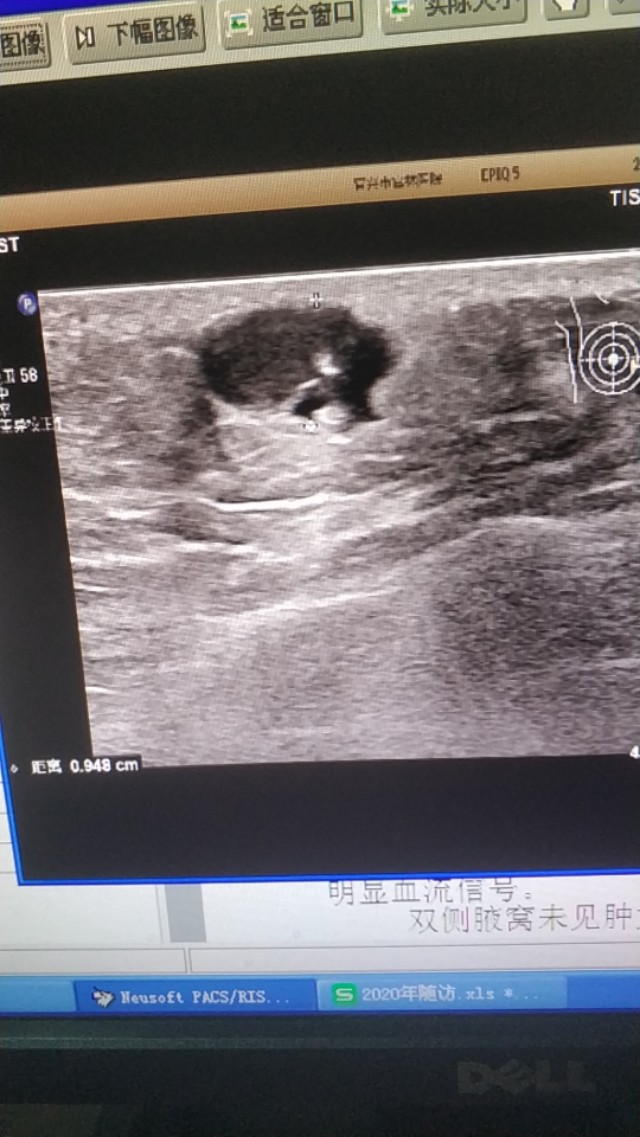

第二点事边界十分清晰,如果囊肿破裂,周围会有积液。第三点是内容物是软化不同的角瓜上皮,超声上表现为细密的腺样强回声有时伴有细密的裂隙样低回声。第四没有血流信号。

上图是一个左膝部的表皮囊肿,与皮肤真皮层关系密切,里面回声细密伴裂隙样低回声。

(这两个病例是上个月随访的)